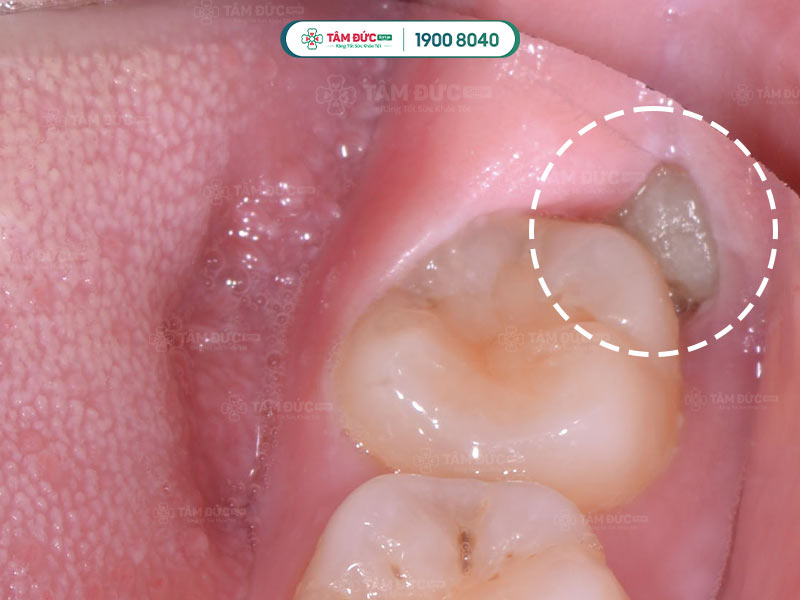

Những đốm trắng xuất hiện phía sau những chiếc răng cuối cùng chính là phần trên của răng khôn đang mọc lên xuyên qua nướu.

Răng khôn không còn đủ chỗ mọc

Răng khôn mọc lệch gây đau nhức và đâm vào răng số 7